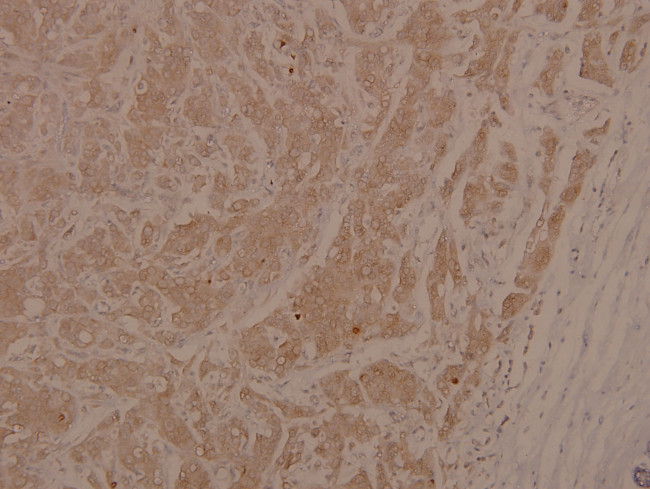

Phospho-ASK1 (Ser966) Antibody in Immunohistochemistry (Paraffin) (IHC (P))

Phospho-ASK1 (Ser966) Antibody (PA5-36619) in IHC (P)

Immunohistochemical analysis of Phospho-ASK1/MAP3K5 pSer966 in paraffin-embedded human breast carcinoma using Phospho-ASK1/MAP3K5 pSer966 polyclonal antibody (Product # PA5-36619) at a dilution of 1:100. {{ $ctrl.currentElement.advancedVerification.fullName }} 验证信息 View more